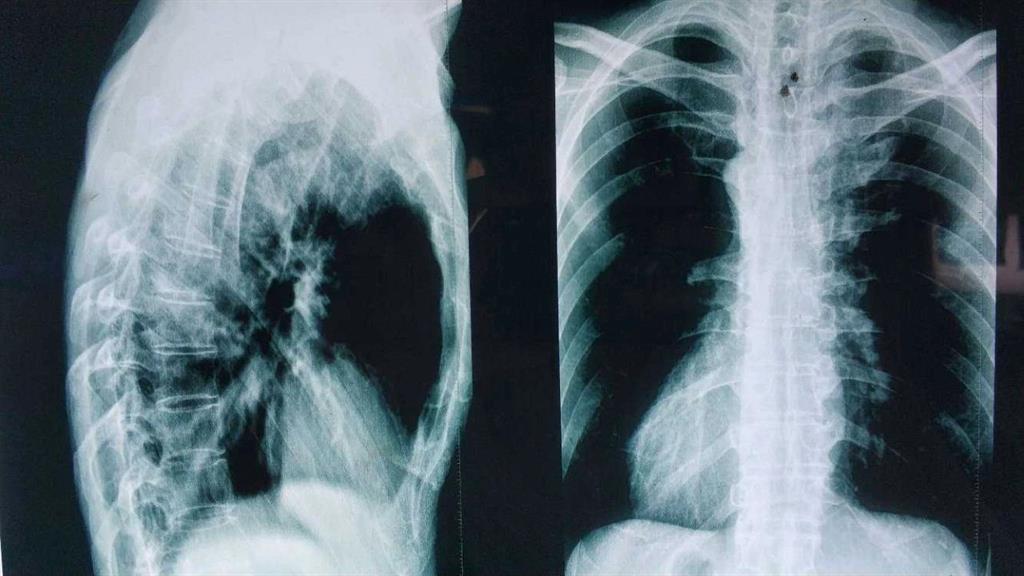

“小伙子!因為你說拍片是為了確實是否為強直性脊柱炎,我們剛才在拍片的時候發(fā)現(xiàn)按照那邊醫(yī)生要求的部位拍攝還是看不到病癥點,所以我們給你拍了兩次,你到時候給醫(yī)生看的時候都給他看。”

“確實挺快的,那邊的醫(yī)生給我拍了兩次你看看。”

醫(yī)生對著拍好的片子來來回回看了好幾遍,男孩就一直站在他邊上,他知道醫(yī)生接下來說的話將決定自己的一生。